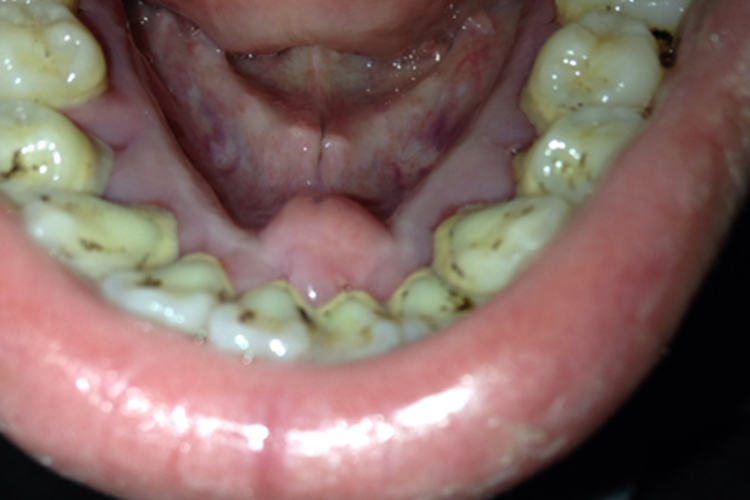

患者的牙龈会有广泛增生,增生的牙龈覆盖部分或整个牙冠,牙常因增生牙龈挤压而发生移位。通常舌下牙龈内侧异常增生的牙龈颜色正常,组织坚韧,表现为硬疙瘩,其表面光滑,点彩明显,不易出血。

纤维型牙龈瘤引起的肿块较局限,可呈圆形或椭圆形,有时呈分叶状,表现为硬疙瘩,大小不一,质地坚韧,色泽与正常牙龈差别不大,表面光滑,不易出血。